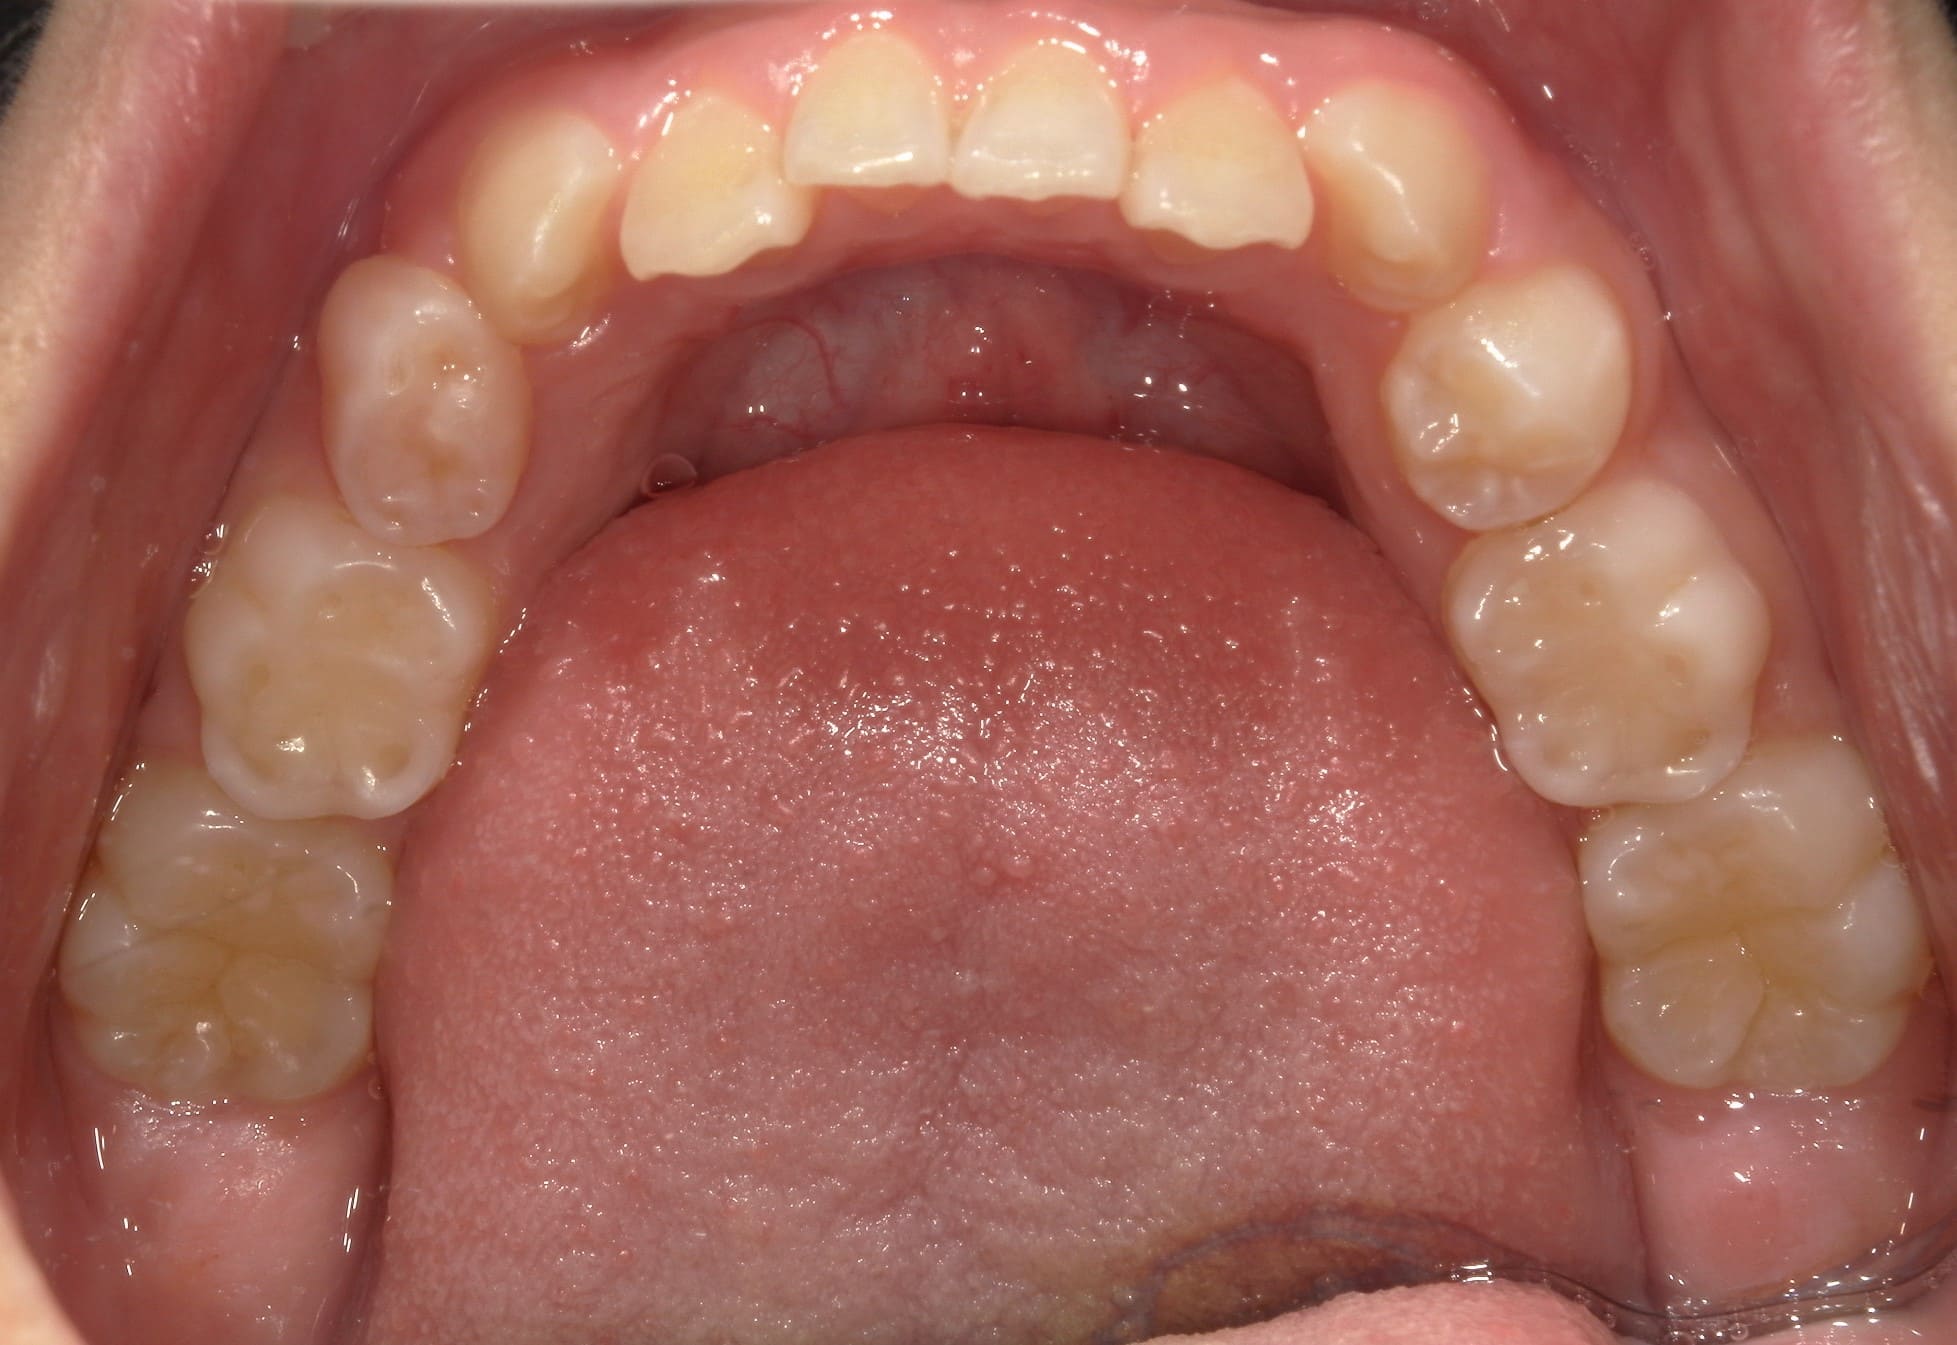

| 年齢・性別 | 7歳1ヶ月の男児 |

|---|---|

| 主訴 | 歯の生えるスペース不足が懸念され、歯列の乱れ(叢生)を整えるために来院された患者様です。 |

| 治療期間・回数 | 1年3ヶ月・11回 |

| 費用 | 420,000円(税別) |